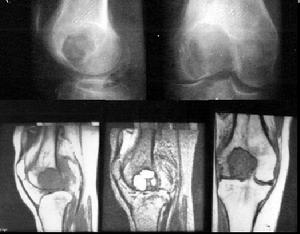

骨良性纖維組織細胞瘤的典型X線表現為病變位於長骨距骺板3~5厘米處,少數可接近骨幹,呈偏心生長,病變破壞原有骨小梁呈透亮狀,髓腔內腫瘤向骨皮質壓迫、擴張、變薄及硬化,邊界清楚,內可有分房,病灶縱軸與長骨一致。若出現病理性骨折,可見到骨膜反應。